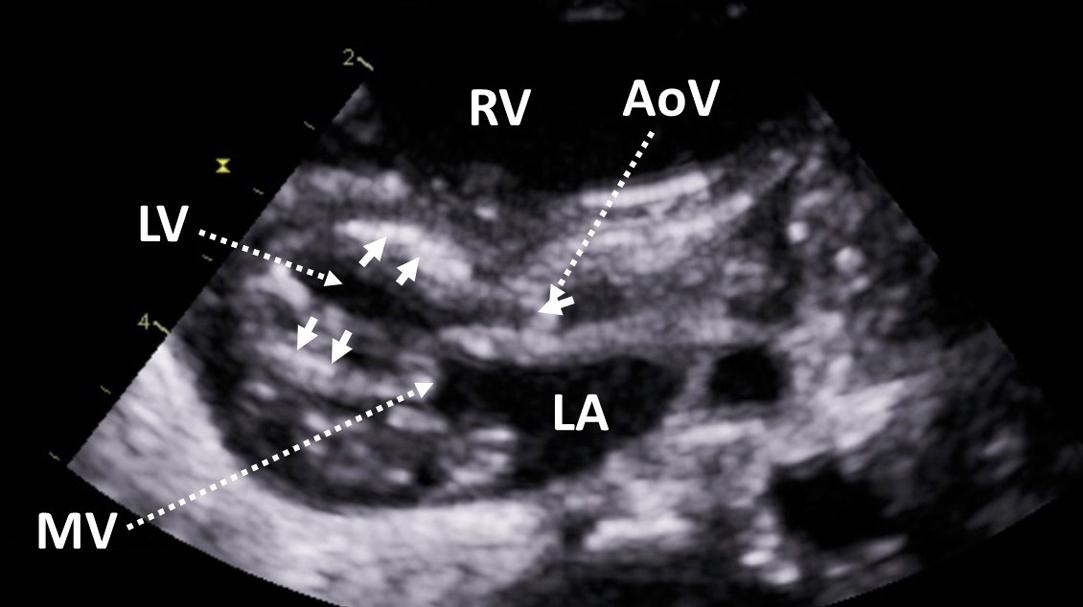

Figure 6, Parasternal long-axis view demonstrating hypoplasia of the left ventricle. The aortic and mitral valves are small and severely stenotic. There is hyperechogenicity of the endocardium consistent with endocardial fibroelastosis ( arrows ). AoV , aortic valve; LA , left atrium; LV , left ventricle; MV , mitral valve; RV , right ventricle.